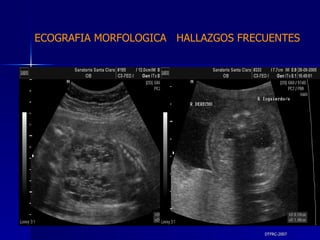

DTFRC-2007 ECOGRAFIA MORFOLOGICA  HALLAZGOS FRECUENTES   MATERIAL Y METODO ES UN ESTUDIO DESCRIPTIVO, RETROSPECTIVO  DE ESTUDIO ECOGRA FICOS REALIZADOS ENTRE MARZO 07 A MARZO 08 EQUIPO DE ALTA RESOLUCION   VOLUSON 730 PRO  MEDISON SA 8000 live MEDISON SA 8000SE CRITERIO DE INCLUSION:   POBLACION GENERAL    GESTACIONES  20 a 24 SEMANAS   UNIVERSO  N 211

DTFRC-2007 ECOGRAFIA MORFOLOGICA  HALLAZGOS FRECUENTES   GENITOURINARIA DISPLASIA RENAL MULTIQUISTICA  3 HIDRONEFROSIS  2 QUISTE DE OVARIO FETAL  1 SISTEMA DIGESTIVO DILATACION INTESTINAL  2  SISTEMA ESQUELETICO   PIE BOT  2  20 % 6 % 6 %

DTFRC-2007 ECOGRAFIA MORFOLOGICA  HALLAZGOS FRECUENTES   OTROS HIGROMA QUISTICO  2 ENFERMEDAD ADENOMATOSA PULMONAR  1 ARTERIA UMBILICAL UNICA  2 HIDROPS FETAL NO INMUNE  1 QUISTE DE CORDON UMBILICAL  1 ALTERACION DE LIQUIDO ANMIOTICO  2 SINDROME TRAFUSIONAL FETO FETAL 1 LABIO LEPORINO  2 TOTAL  12  42 %